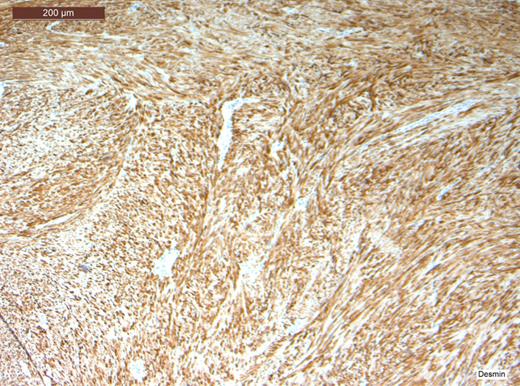

Histopathological analysis of the lesion, including immunohistochemical profiling, revealed a well-circumscribed nodular tumour composed of smooth muscle cells with eosinophilic cytoplasm and spindle-shaped nuclei. The cells were arranged in interlacing fascicles with evidence of perinuclear vacuoles using haematoxylin and eosin staining. There was no evidence of necrosis, mitosis or significant nuclear pleomorphism. The specimen was negative for CD117 staining, hence excluding the possibility of a gastrointestinal stromal tumour. It was also negative for S100. However, stain was positive for smooth muscle actin (SMA) and desmin, which confirmed that specimen was of muscular origin. The histology therefore identified the lesion as a leiomyoma (Figs 2–6).